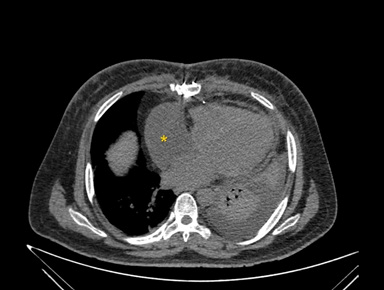

The differentials considered were intracardiac right atrial thrombus, localised pericardial effusion and extracardiac mediastinal bleed in view of recent surgery and use of anticoagulants, antiplatelets. To differentiate above conditions, Computerised Tomography (CT) scan of the chest considered which revealed a mediastinal hematoma of 8.8 x 8.0 cms external to right atrium causing invagination into the RA causing right atrial tamponade (Figures 3,4). He underwent exploratory surgery on the 10th postoperative day, during which the bleed was evacuated, normalizing right atrial function and relieving the inlet obstruction on the RV.

Figure 3: Computerized tomographic axial view of right atrial extra cardiac collection indicated by yellow asterisk (*).